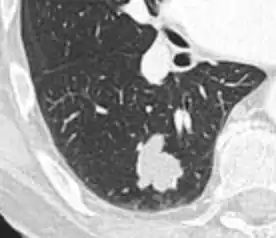

Round well-delineated solid lung nodule with smooth border.[9]